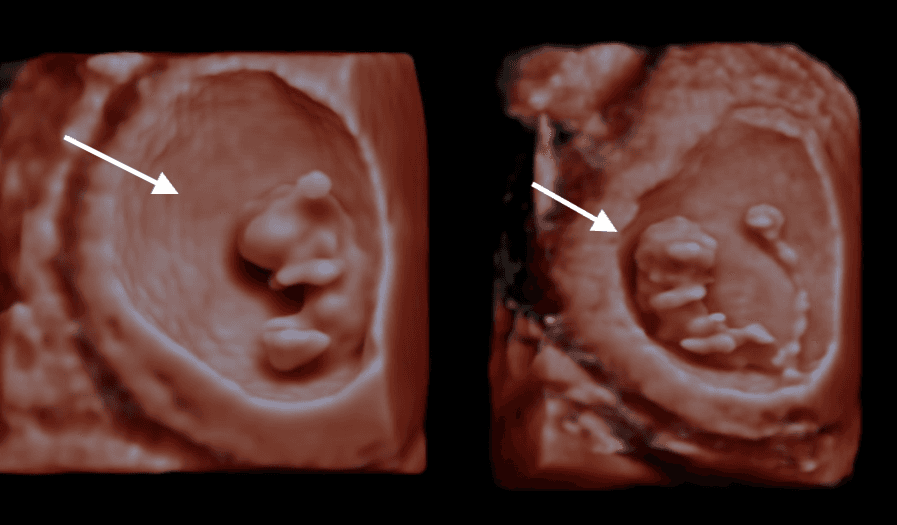

In this video and photos, we are showing you a sample of what you would see at 9 weeks gestation during an early pregnancy scan.

At 9 weeks, your baby is around 2.3cm long (about the size of a grape) and you can typically see:

- The heartbeat - beating strongly at around 170 bpm

- Head and body - distinct but still proportionally large head

- Tiny limb buds - arms and legs beginning to form

- Movement - your baby may already be wriggling!